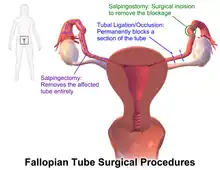

Surgery

The surgical removal of a fallopian tube is called a salpingectomy. To remove both tubes is a bilateral salpingectomy. An operation that combines the removal of a fallopian tube with the removal of at least one ovary is a salpingo-oophorectomy. An operation to remove a fallopian tube obstruction is called a tuboplasty. A surgical procedure to permanently prevent conception is tubal ligation.

Blockage or narrowing

If a blocked fallopian tube has affected fertility, its repair where possible may increase the chances of becoming pregnant.[21] Tubal obstruction can be proximal, distal or mid-segmental. Tubal obstruction is a major cause of infertility but full testing of tubal functions is not possible. However, the testing of patency – whether or not the tubes are open can be carried out using hysterosalpingography, laparoscopy and dye, or hystero contrast sonography (HyCoSy). During surgery, the condition of the tubes may be inspected and a dye such as methylene blue can be injected into the uterus and shown to pass through the tubes when the cervix is occluded. As tubal disease is often related to Chlamydia infection, testing for Chlamydia antibodies has become a cost-effective screening device for tubal pathology.[22]